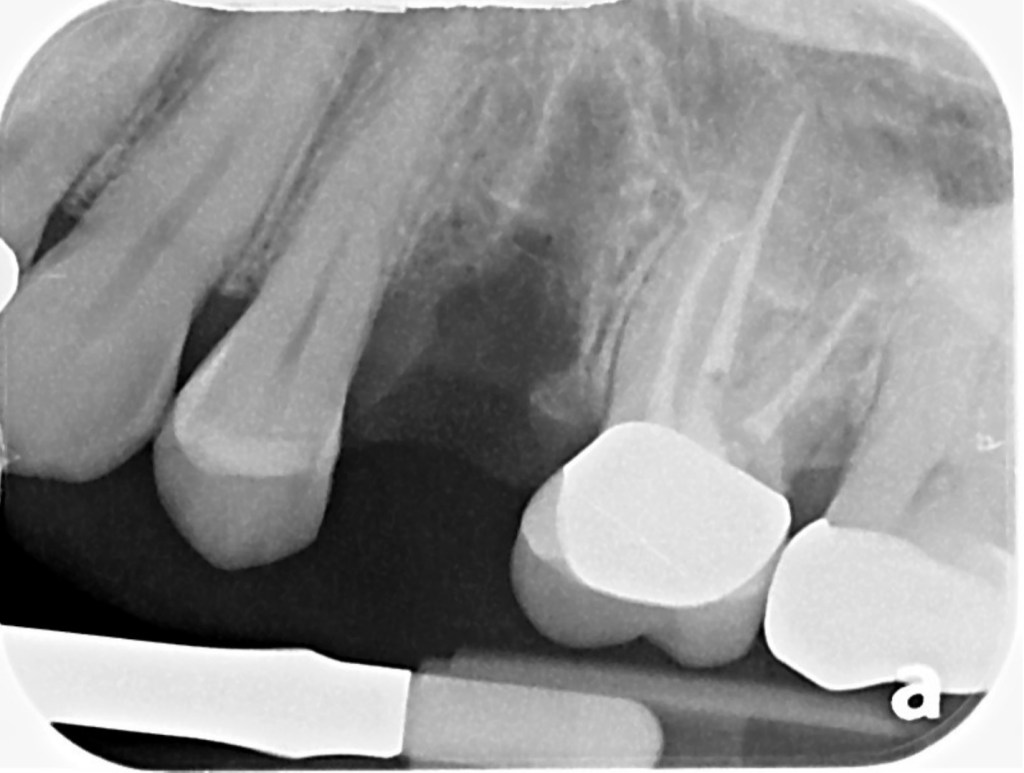

Here is how it looked 6 months later. Implant time.